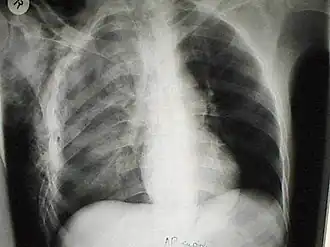

Подко́жная эмфизе́ма — скопление воздуха в подкожной клетчатке грудной стенки, распространяющееся на другие области тела. Является симптомом повреждения лёгкого или воздухоносных путей[1].